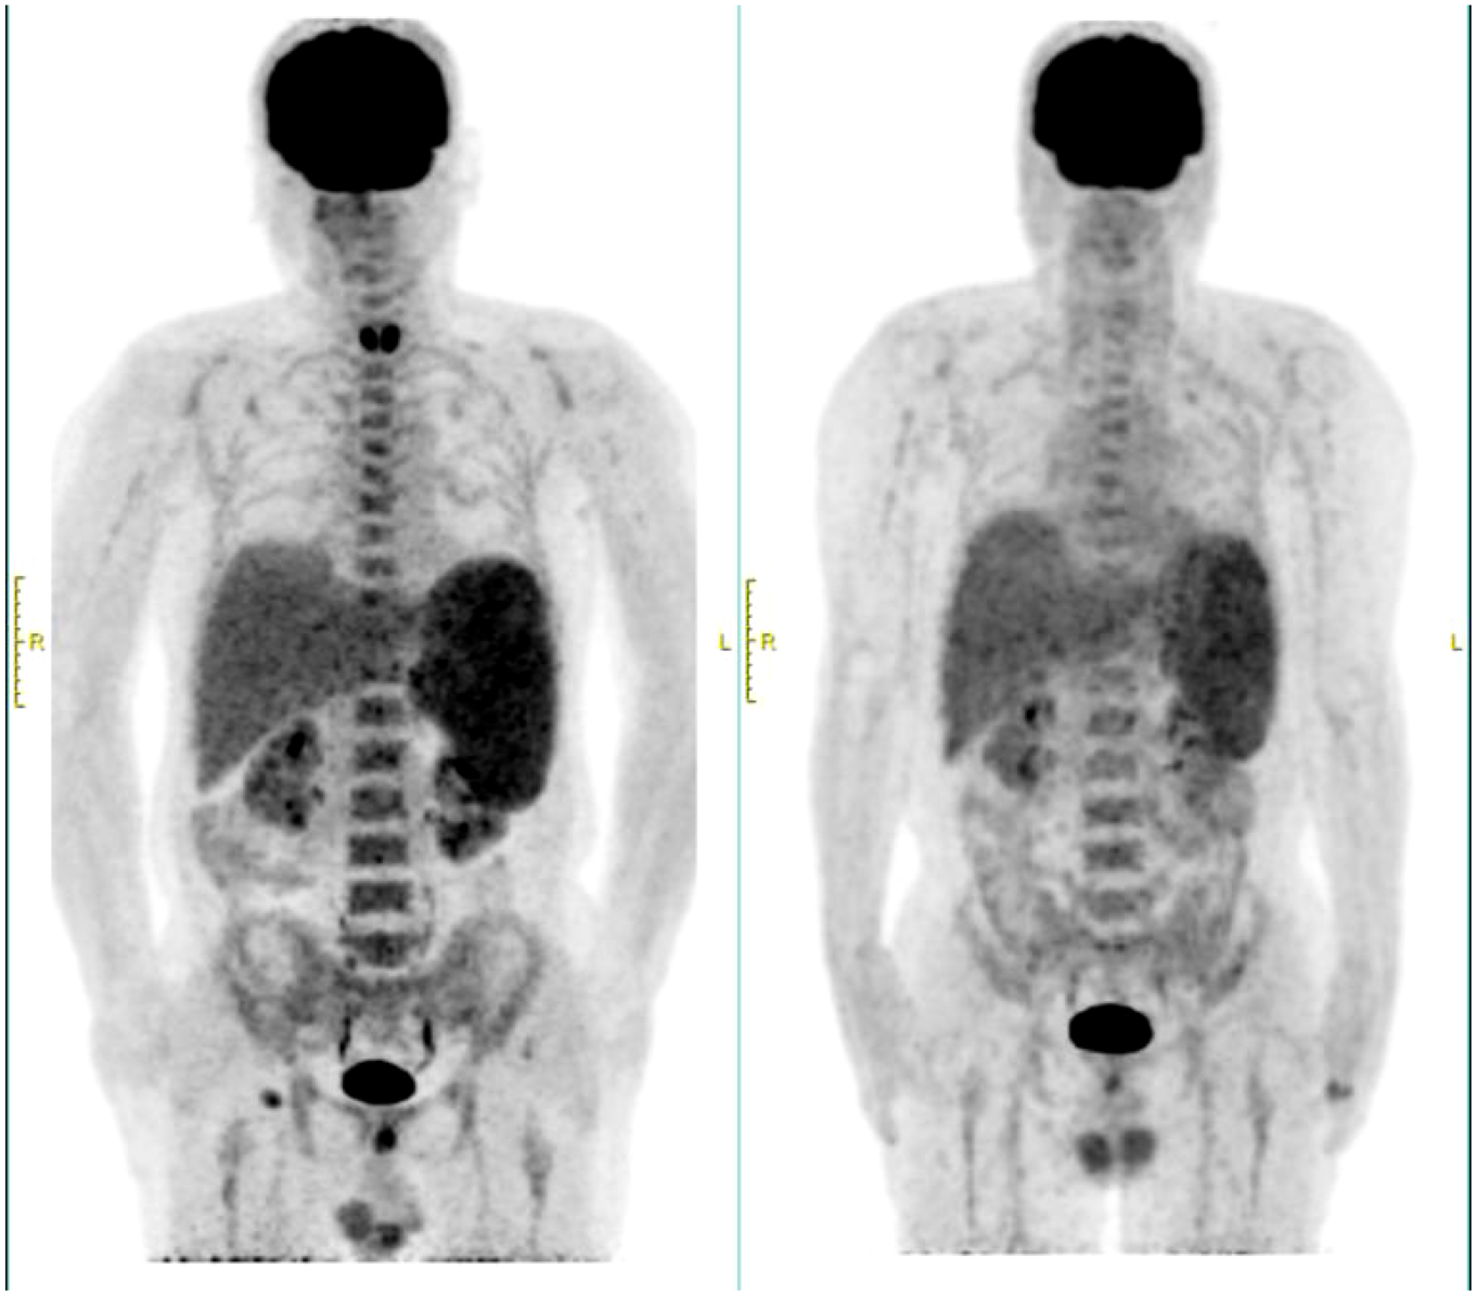

In March 2024, the patient experienced recurrent fever up to 39°C and significant fatigue. Despite anti-infection treatments at a local hospital, symptoms persisted, leading to readmission. Laboratory findings included a white blood cell count of 2.72×109/L, neutrophil count of 2.03×109/L, hemoglobin of 97 g/L, and platelet count of 103×109/L. Compared to the initial diagnosis PET-CT, the current scan reveals hepatosplenomegaly with increased metabolic activity, diffusely homogeneous hypermetabolism throughout the skeletal system, and enlarged hypermetabolic lymph nodes in the right inguinal region (Figure 1). The percentage of abnormal NK cells in bone marrow was 25.6%. HE and PAS staining showed active bone marrow hyperplasia (about 50%), atypical lymphocytes aggregation accounted for 10% of nuclear cells, reduced cytoplasm, irregular nuclei, fine chromatin, and visible nucleoli. The tumor cells were positive for CD2, CD56, TIA-1 and Granzyme B, but negative for CD3 and CD5. Karyotype analysis revealed 44, X, -Y, i (7) (q1), del (9) (p21), der (10, 11) (q10; q10), inv (12) (p11.2q25) [3]/46, XY [27]. EBV-DNA quantification was normal. Serum ferritin: 1396ng/ml. Combined with the clinical manifestations of persistent fever, hepatosplenomegaly, and significantly elevated ferritin, the diagnosis was revised to EBV-negative ANKL.

Figure 1

PEC/CT at recurrence and initial diagnosis. The left side was at recurrence in March 2024, and the right side was at initial diagnosis in August 2023.